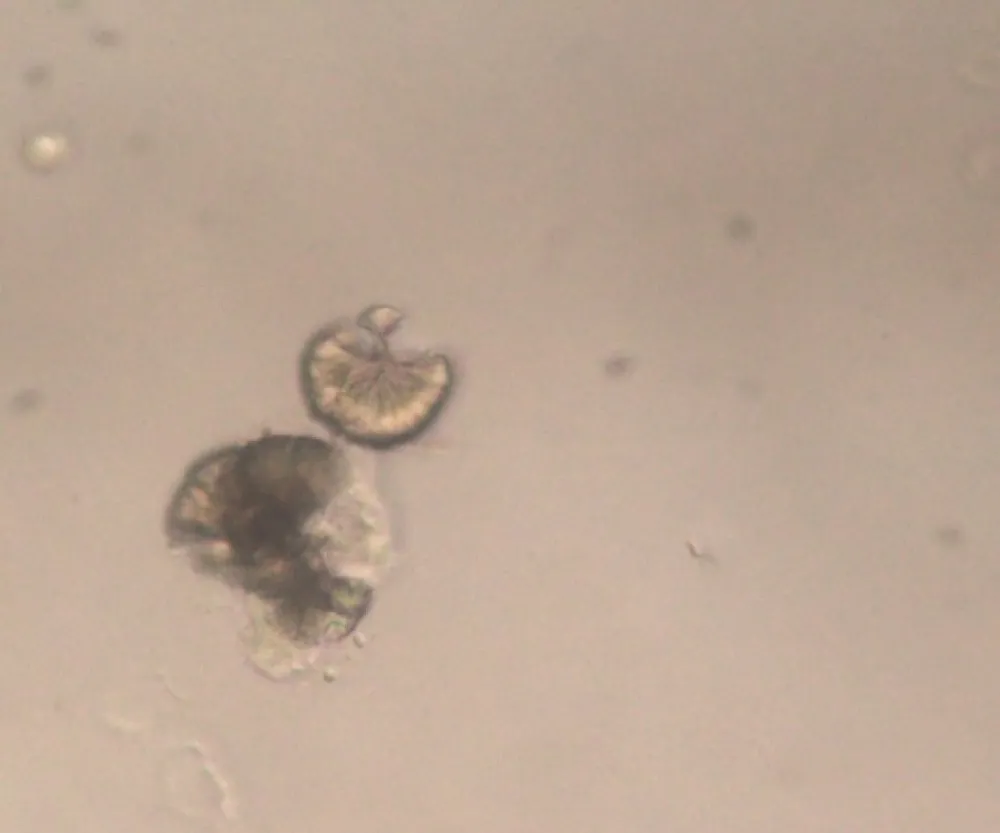

Por que contraindicamos o uso de vitamina C no paciente com DRC dialítica? Confere esse caso clínico no NEJM

Diversas são as causas de IRA, temos que ter muita atenção para não nos contentarmos com casos de IRA sem etiologia definida. Confere esse caso peculiar.